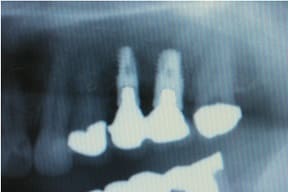

CASE03 臼歯部インプラント ~ブリッジがグラつき始めている~

ブリッジの部分の下顎の骨が吸収をおこし、ブリッジで支えている歯がぐらつき始めている状態。予後を考えた結果、ブリッジで支えることが困難という診断のもと、インプラント治療を施したケースです。